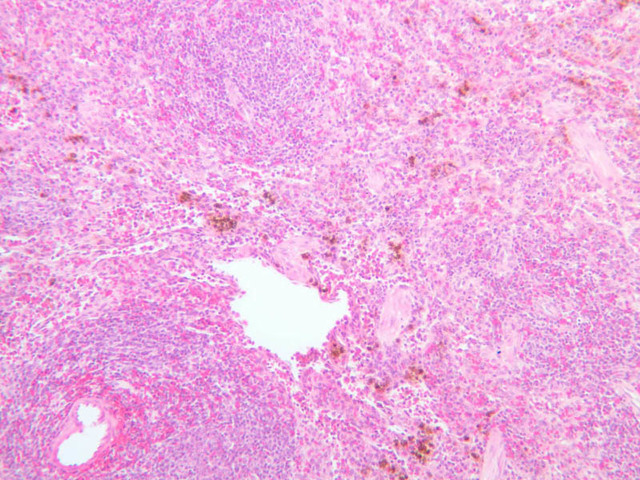

Sections through the spleen (slides A-36, aniline blue [2.5x, 10x, 20x-labeled, 40x] [2.5x, 10x-labeled, 20x-labeled, 40x]; A-37, retic [2.5x, 10x, 20x-labeled, 40x]; A- 37, H&E [2.5x-labeled, 10x, 20x, 40x]; A-38, H&E [10x, 20x, 40x]; A-39, H&E [2.5x, 10x, 20x, 40x]) show a thick investing capsule composed of collagenous tissue and smooth muscle, typically covered with mesothelium. In slide A-36 muscle and collagen are brightly stained. The capsule and mesothelium completely surround the organ and the fibrous portion enters the splenic substance at the hilus around the splenic arteries and veins forming trabeculae of fibromuscular tissue within the splenic substance. This fibromuscular tissue enables the spleen to expel blood by contracting. Identify trabeculae as fibrous partitions in the section and look for blood vessels within them.

Where the trabecular arteries pass into the splenic pulp, they become invested by a sleeve of lymphoid tissue. This lymphatic tissue collectively forms the white pulp of the spleen (A-36 [2.5x, 10x, 20x, 40x]). It also is referred to as the periarterial lymphatic sheath or PALS. On an H&E stained section (A-38 [2.5x, 10x, 20x, 40x] [2.5x, 10x, 20x, 40x]) the white pulp will appear as basophilic clumps of lymphoid cells. The arteries of the white pulp are called central arteries, although they may be displaced to one side of the lymphoid sleeve by the presence of a nodule. The majority of cells forming the PALS are T lymphocytes. In places the covering of lymphatic tissue is enlarged due to the presence of lymphoid nodules (splenic or Malphighian corpuscles) which are comprised predominantly of B lymphocytes.

The remainder of the cellular mass in the spleen is red pulp (A-38 [10x, 20x, 40x]), made up of red and white cells of the blood enmeshed in the reticular tissue of splenic cords and present in the splenic sinuses. After passing through the PALS, the trabecular arteries branch to form smaller arterial vessels known as penicillar arterioles which narrow, forming arterial capillaries that empty into the cords of the red pulp (open circulation) or into the venous sinuses (closed circulation). In the splenic sinuses the cells of the blood are exposed to red pulp macrophages. The splenic sinuses eventually become confluent to form veins that enter the trabeculae and gradually merge meeting in the hilus to form splenic veins.

Examine the composition of the red pulp tissue. The three dimensional structure of the red pulp is analogous to Swiss cheese with the holes being the venous sinuses and the cheese being the parenchyma (i.e. splenic cords). On slide A-36 which is stained with Mallory's aniline blue locate examples of the splenic sinuses ([2.5x, 10x, 20x, 40x-labeled] [10x, 20x, 40x]). The walls of the splenic sinuses consist of adjoining specialized endothelial cells whose nuclei in many cases stand out from the wall in a bead-like fashion. The basement membrane of the epithelial cells stains blue revealing the sinuses quite nicely. Usually the sinus lumen is filled with red cells and leukocytes. The skeletal framework of the cords is provided by a network of reticular fibers. As above, the reticular cells are best seen using a reticular fiber stain (slide A-37 [2.5x, 10x, 20x, 40x-labeled]). Look for the large pale nuclei of reticular cells that have darkly stained reticular fibers. Fibers run irregularly in the cords, but clearly outline the sinuses around which they are wrapped. Notice on this same slide that there is much less reticular tissue in the white pulp than the red. The splenic cords occur around the sinuses and are distinguished by the presence of disintegrating red blood cells undergoing phagocytosis.

Here's a little histopathology: Observe slide A-40 (H&E [2.5x, 10x, 20x, 40x]). In this slide the corpses of red blood cells appear brown and can be seen littered throughout. These residual RBCs are referred to as hemosiderin. Slide A-39 (H&E [2.5x, 10x, 20x, 40x]) was prepared from a patient undergoing chemotherapy. How does the white pulp in this slide differ from the normal spleen, slide A-38?